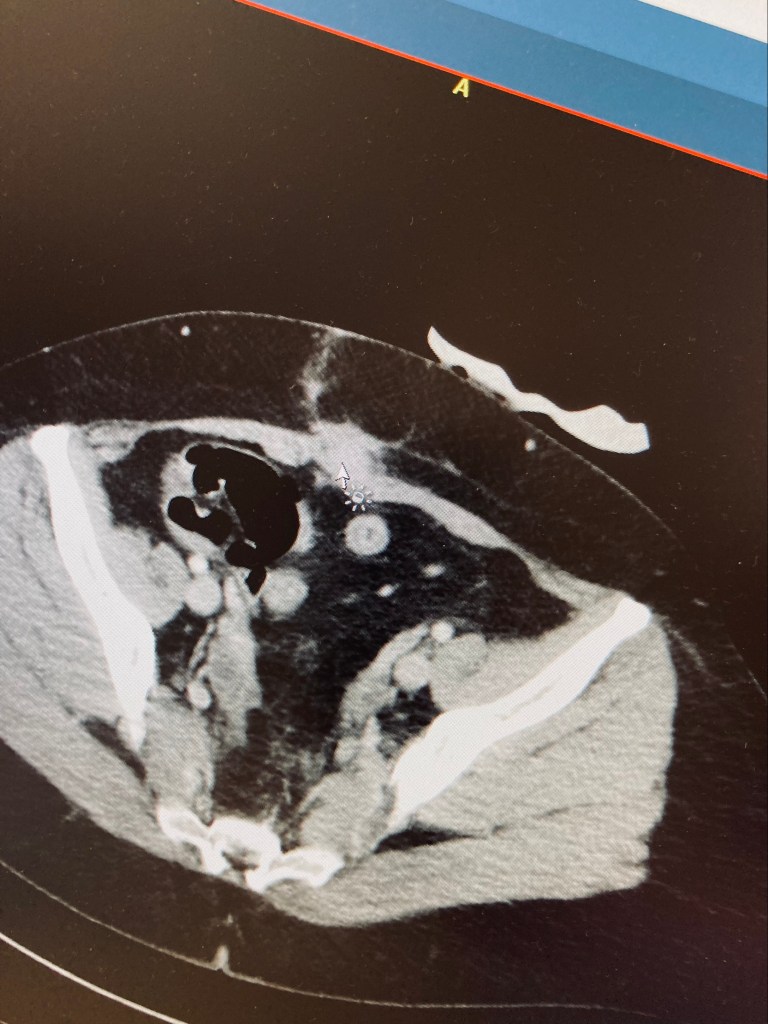

Ich ging zu meinem Gastro-Alles-Hausarzt, weil ich wusste, er würde wenigstens versuchen, eine Lösung zu finden. Dank meines Blogs war mir Endometriose ein Begriff und obwohl ich die Zusammenhänge nicht verstand, hatte ich genau diese Diagnose im Verdacht. Er hatte keine große Hoffnung, im Ultraschall etwas zu entdecken – machte ihn aber trotzdem. Erst fand er nichts, bis er stockte und sich ein 2cm großer echoarmer Bereich bei der drei Jahre alten Kaiserschnittnarbe auftat. Auch ohne Periode tat der Bereich bei Druck sehr weh, aber was das war, blieb unklar. Ein CT war der nächste Schritt, kurz vor der nächsten Periode lag mein Termin. Volles Programm: Kontrastmittel trinken und Kontrastmittel spritzen, dann schnell Bildmaterial erstellen. Danach arbeiten gehen und hoffen, in ein paar Tagen schlauer zu sein. Drei Tage später leider die Enttäuschung, dass man nicht sagen konnte, was es war. Keine Zyste, kein mit Flüssigkeit gefüllter Raum. Festes Material, was da irgendwie nicht hingehörte. Weiter ohne tatsächlichen Anhaltspunkt, machte ich einen Termin bei meinen Chirurgen in der Klinik. Wieder drei Wochen warten, hieß das. Eine weitere Periode aus der Hölle, hieß das. Direkt vor unserem Urlaub kam sie dann, das Meiste Gott sei Dank davor. Aber auch im Urlaub hatte ich teils mit Schmerzen zu kämpfen, besonders wenn wir laufen waren oder Abends dann, wenn der Körper zur Ruhe kam. Groß was dagegen tun, konnte ich nicht. Bisher hatte ich leider auch kein Erfolg mit Wärme. Wenn die tatsächliche Blutung ein paar Tage zurückliegt, klingen die meisten Schmerzen nach und nach langsam ab.

Ohne aktive Periode aber mit Termin fuhr ich mal wieder nach Ravensburg in die Klinik. Wenigstens nicht die Notaufnahme. Nach der normalen Parkplatzsuche des Wahnsinns – wenn die Menschen doch nur besser parken würden – wartete ich auf meinen Termin beim Oberarzt. Aber dem saß ich nicht gegenüber, sondern einem jungen Chirurg, der mir weder sympathisch noch offen schien. Ich sah meine Chancen in dem Moment schon schwinden und Angst kam in mir auf. Trotzdem versuchte ich ihm offen zu schildern, warum ich mit meinem CT-Material gekommen war. Mit jedem Satz sah ich in seinem Augen den Zweifel an mir wachsen und ich fühlte mich mit jedem Satz hilfloser. Er fragte, ob ich das CT angesehen hätte, denn er würde darauf nichts entdecken, was so Schmerzen machen würde. Ich erwiderte ihm, dass ich Schmerzen hätte und ich so nicht wieder gehen würde ohne einen Lösungsansatz. Dann verschwand er und ich saß 15 Minuten alleine dort mit meinen Gedanken. Dass ich gleich in meiner alten Klinik einen Termin vereinbaren würde, noch auf der Rückfahrt. Alle möglichen unschönen Gefühle krochen hervor. Danach ging alles irgendwie schnell, denn da stand er, der gewünschte Oberarzt der Chirurgie und ich schöpfte Hoffnung. Ob er einen Ultraschall machen dürfte, meine Beschreibungen wären sehr präzise gewesen. Meine Hoffnung wuchs. Eh ich mich versah, stand auch der Oberarzt der Gynäkologie im Raum. Ja, das wäre sehr gut zu erkennen, sagte er. Da lag ich nun und war nicht sicher, was da passierte. Aber es passierte. Nur wenige Minuten später verließ ich den Raum in Begleitung des Oberarztes der Gynäkologie – denn anscheinend war es wie im Bilderbuch: eine gesprengte Endometriose, künstlich ins Leben gerufen nicht von mir, sondern durch den Kaiserschnitt. Nicht so selten, laut Klinik. Bei der Geburt wurden Zellen verteilt und nicht wieder eingesammelt, diese sind in drei Jahren nun langsam gewachsen. Das würde man immer häufiger sehen. Er nahm mich aus der Chirurgie mit, so einfach hatte ich noch nie den Fachbereich gewechselt. Obwohl ich mit etwas konfrontiert war, was ich nicht wollte, war ich erleichtert. Ich fühlte mich gehört, gesehen und irgendwie glücklich. Beim Oberarzt fühle ich mich abgeholt und verstanden. Ich war dankbar. Einfach dankbar. Ganz bizarr, diese Gefühle in diesem Moment.